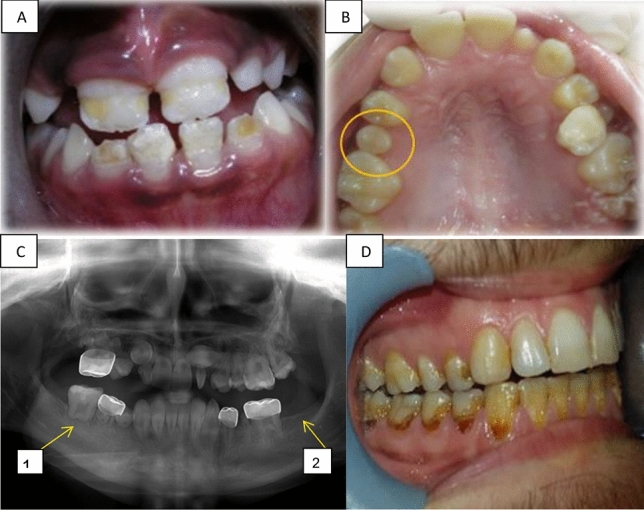

Table 2 presents the numbers of participants and the numbers of teeth with each dental anomaly. In total, 56 (46%) patients had at least one DDA, in 309/3388 teeth (9%). Hypomineralization or hypoplasia of enamel presented in 21 (17%) patients (Fig. 1A); and the same number of microdontic teeth presented (Fig. 1B). Altered root development presented in 26 (21%) patients (Fig. 1C1) and hypodontia in 13 (11%) (Fig. 1C2). Table 3 presents DDA according to anticancer treatment modalities. Malformed teeth were detected in 36/83 (43%) patients who had received only chemotherapy, 20/38 (53%) of those who had received radiation, 15/36 (42%) of those who underwent BMT, and 9/15 (60%) of those who had received radiation to the head and/or neck. The age at initiation of oncology treatment ranged from 0 to 18 years. The proportion of patients with malformed teeth was higher among those who initiated treatment at age 6 years or younger (31/55, 56%) than among those who initiated treatment between ages 6 and 12 years (19/43, 44%) (Table 4). In addition, all the types of DDA were more frequent in individuals who initiated anticancer treatment at age 6 years and younger (Table 4).

Figure 1.

Long term dental effects. (A) Hypoplasia in the front upper and lower teeth of a girl aged 9 years, treated for ALL at age 3.5 years. (B) Microdontia showing the second upper right premolar in a girl age 12 years, treated for neuroblastoma at age 4 years. (C) A panoramic radiograph of a 12-year-old boy diagnosed with Burkitt's lymphoma at age 4 years, revealing: C1. Altered root development at the first lower right molar, C2. Hypodontia of the second lower left molar. (D) Radiation caries in a 21-year-old boy treated for neuroectodermal tumor at age 14 years.

The mean DMFT score for the study group was 6.69. This score is much higher than 1.66, which was reported for healthy 12-year-old children in Israel31. In the present study, the 'DT' component was the highest. Our findings concur with other reports of higher incidence of caries in children who received antineoplastic therapy12,15,21,29. For our patients who received radiotherapy, the DMFT was even higher, 8.37; this compared to a score of 5.93 among patients who received only chemotherapy. Aggressive and extensive caries, commonly known as radiation caries (such as seen in Fig. 1D), have a rapid onset and progression12. Radiation caries result from the sequelae of xerostomia, teeth hypomineralization or hypoplasia, and a cariogenic shift in microflora30. Teeth demineralization following radiotherapy can be remineralized30,32. To avoid the development of osteoradionecrosis following radiotherapy, and to avoid the loss of teeth, dentists should be conservative and try to preserve teeth with endodontic and restorative treatment12.